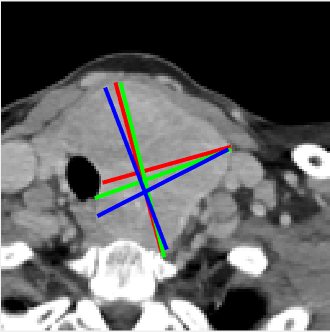

Figure 3: Given the input test image (a), we can obtain the predicted lesion mask (b), the transformed image (c) from the STN, and the estimated keypoint heatmaps (d)-(g) from the SHN. From (d)-(g), we obtain the estimated RECIST (h), which is close to the annotations (i) labeled by radiologists. Red, green, and blue marks denote DL, R1, and R2 annotations, respectively.

Fig. 3 shows five visual examples of the results. Fig. 3(b) and 3(c) demonstrate the effectiveness of our STN for lesion region normalization. With the transformed image (Fig. 3(c)), the keypoint heatmaps (Fig. 3(d)-(g)) are obtained using SHN. Figs. 3(d) and 3(e) are the heatmaps of the left and right endpoints of long diameter, respectively, while Figs. 3(f) and 3(g) are the top and bottom endpoints of the short diameter, respectively. Generally, the endpoints of long diameter can be found more easily than the ones of the short diameter, explaining why the highlighted spots in Figs. 3(d) and 3(e) are smaller. As Fig. 3(h) demonstrates, the RECIST estimation correspond well with those of the radiologist annotations in Fig. 3(i). Note the high inter-reader variability.